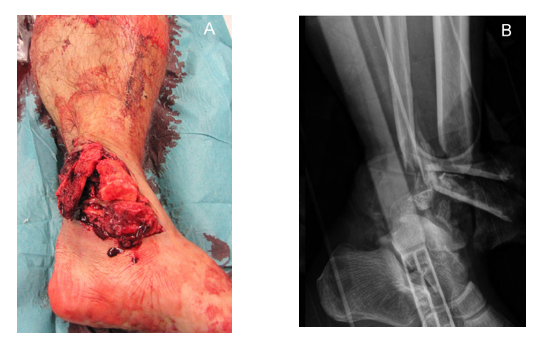

53y  M  车祸损伤左侧胫腓骨远端开放性粉碎性骨折Gustilo IIIB;AO 43-C3

Stage I清创、外支架固定

• 骨缺损6cm

• 软组织缺损

• 距骨关节面外露

带抗生素骨水泥旷置游离股薄肌瓣覆盖

术后复查外支架维持稳定Spacer位置理想力线良好